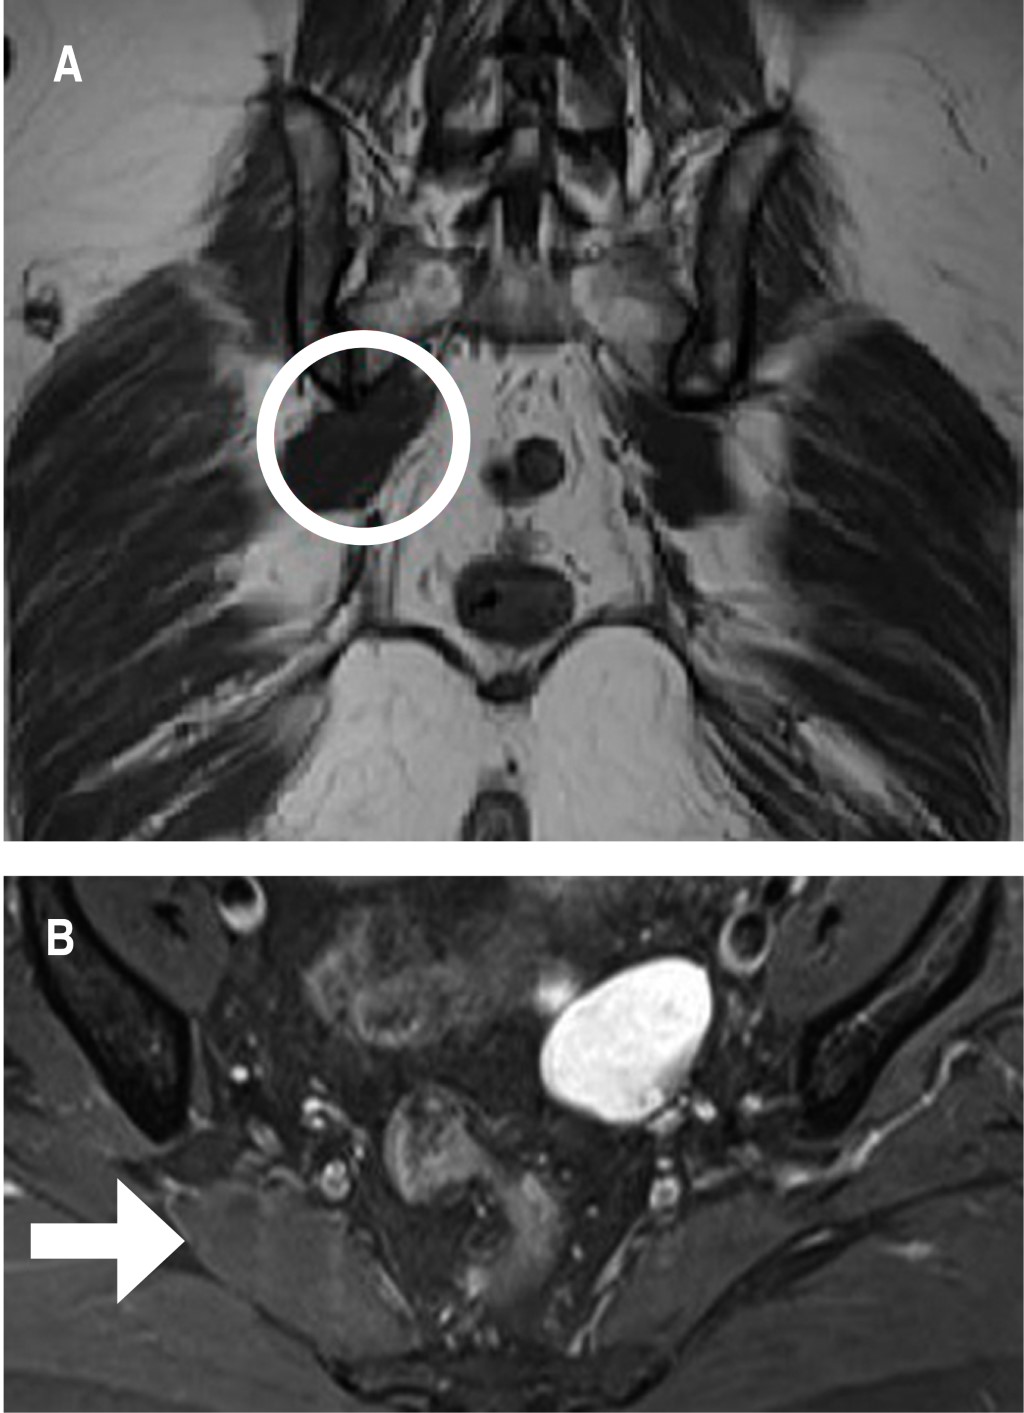

Mujer de 52 años de edad con dolor de glúteo derecho con irradiación a la rodilla y pie de tres meses de evolución, refiere que el dolor aumenta al estar sentada sin tolerar más de 20 minutos. El examen físico: EVA 7/10 y Oswestry 42, Lasegue negativo, FABER y FADIR positivos, reflejos normales, estudios de imagen (RMN) evidenciaron hernia lumbar L 5/S1 sin compresión radicular (Figura 1), además de estudios de electromiografía, interpretado por neurofisiólogo, quien reporta irritación radicular L 5/S1, debido a resultados se inicia tratamiento médico con pregabalina de 75 mg cada 12 horas, acetaminofén/tramadol cada 12 horas, y terapia física y rehabilitación, a pesar de tratamiento durante seis semanas persiste con sintomatología, sin mejoría clínica, porque se realiza infiltración foraminal de S1 guiada por fluroscopia, sin presentar mejoría. Se realiza nueva exploración clínica, y en esta oportunidad presenta prueba FADIR con dolor aumentado, y dolor a la palpación en región glútea, por lo que se realiza RMN de pelvis encontrando asimetría del músculo piramidal, con mayor tamaño de lado derecho (Figura 2), hallazgos que sugieren síndrome piramidal, por lo que se realizó infiltración diagnóstica, la cual fue positiva con alivio del dolor por tres meses (Figura 3). Después inicia otra vez con dolor, nuevamente con prueba FADIR positiva y un EVA de 6/10, se ofrece tratamiento quirúrgico a paciente el cual acepta.

El diagnóstico del SP se ha basado principalmente en presentaciones clínicas, incluyendo dolor de glúteos que se extiende desde el sacro hasta el trocánter mayor; sensibilidad del músculo piramidal a la palpación local y empeoramiento de los síntomas al estar sentado durante un tiempo prolongado.1,3-5 En el este caso, la paciente presentaba síntomas de irritación radicular, aunque las pruebas clínicas no eran concluyentes, la RMN evidenció hernia de disco L 5/S1 pero sin compresión radicular, el estudio de electromiografía reportaba irritación radicular L 5/S1 que podría ser el causante de los síntomas. Por lo tanto, hubo discrepancia entre los hallazgos radiológicos y electromiográficos. Se han reportado hallazgos electromiográficos sin compresión radicular que pudieran sugerir síndrome piramidal. Los estudios son más importantes para descartar patología subyacente.6-8 La RMN de pelvis ha sido útil para observar el volumen del músculo piramidal, así como asimetrías y alteraciones anatómicas del trayecto del nervio ciático, como fue el de este caso.

Figura 1

Figura 2